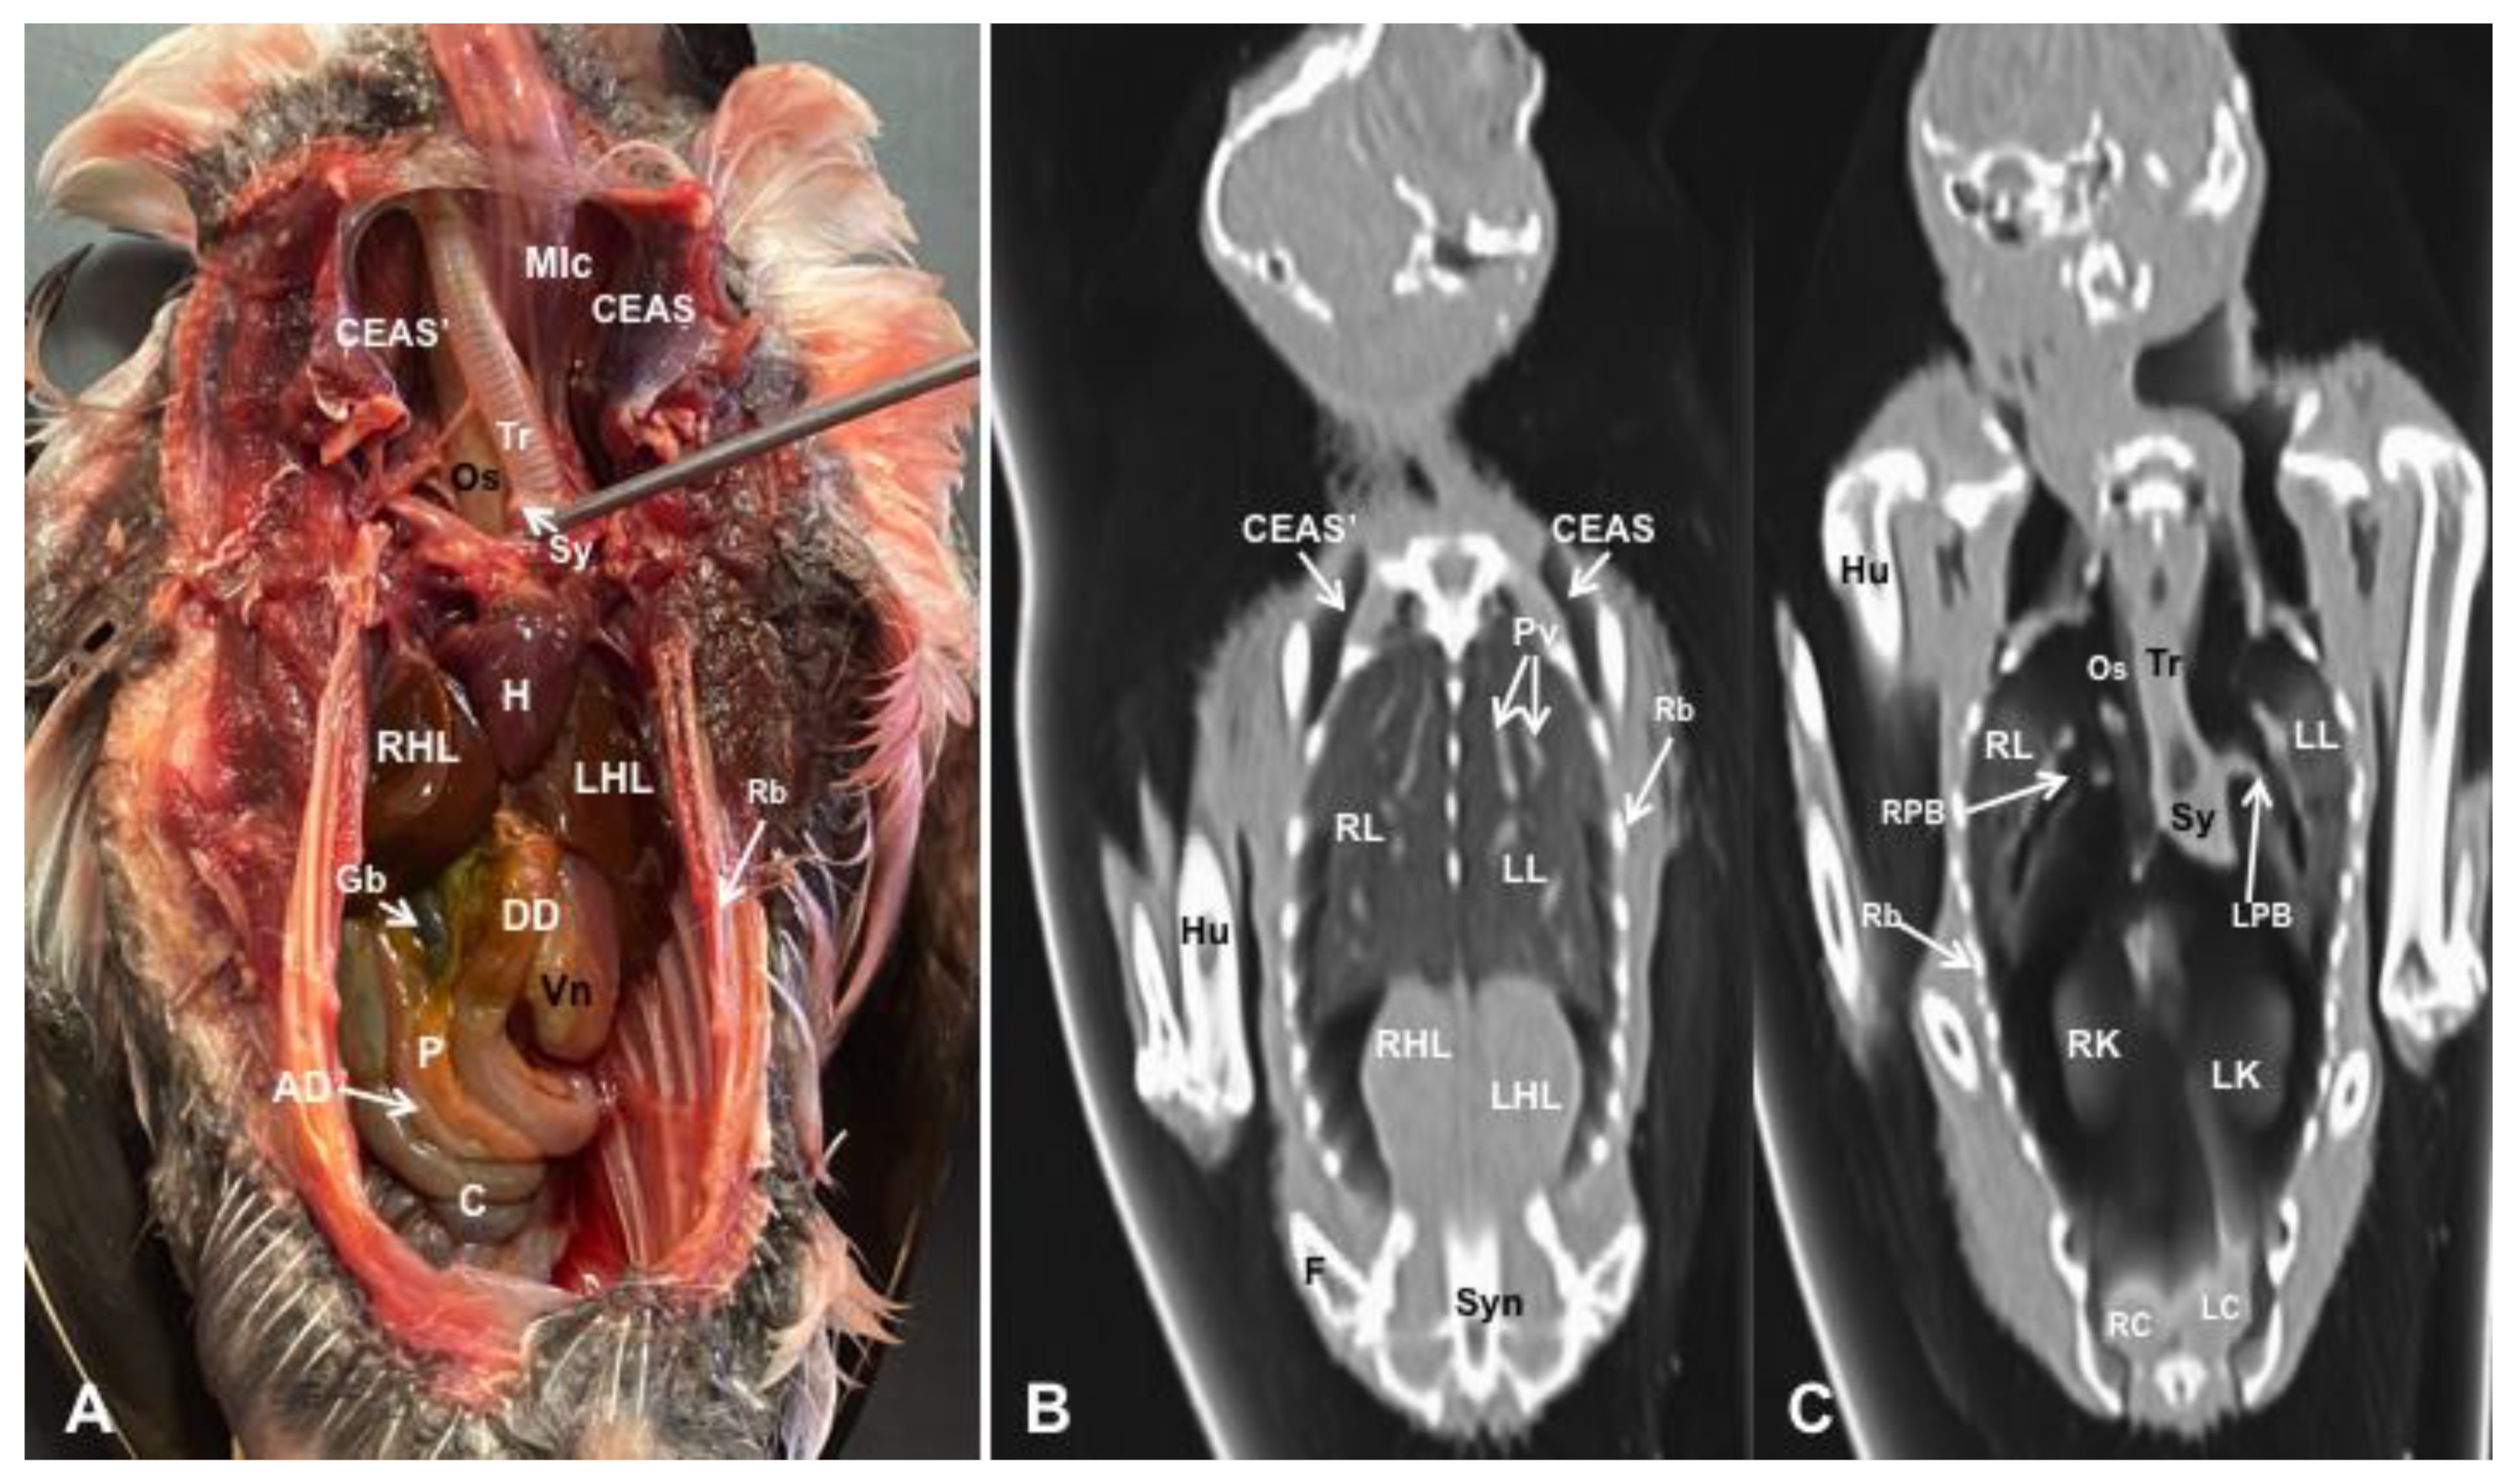

3.1. Anatomical Dissections and Cross-Sections

3.2. Computed Tomography Images